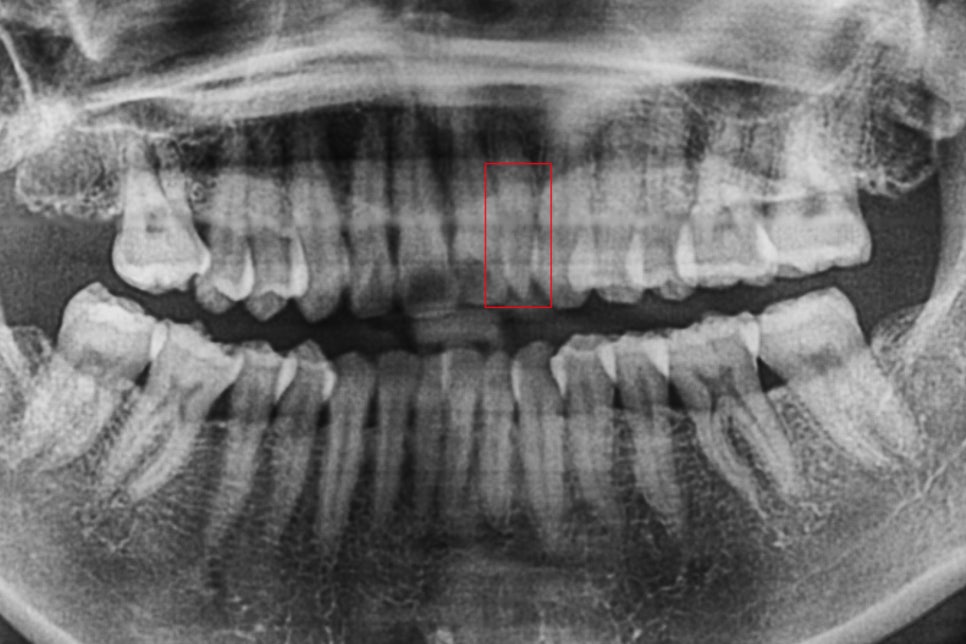

신논현역치과 교정 전 파노라마 엑스레이 사진을 보시면

상악 측절치의 치근과 형태를 확인할 수 있습니다.

확실히 주변 치아와 비교하여 치근이 짧고

뒤틀림이 심한 모습인데요,

이렇게 맹출된 부분이 지나치게 작거나

짧은 경우 치아의 함입을 의심해 볼 수 있습니다.

왜소치 증상을 보철치료로 수복한 후

파노라마 엑스레이 사진입니다.

상악측절치 부분을 보시면 기존의 짧았던

측절치를 신경치료 후 지대치 처리하여

치아의 크기를 커버한 것을 확인할 수 있는데요,

이처럼 보철치료 시 지대치를 만드는 경우

보철물 내부에서 기둥의 역할을 할 수 있어야 하기 때문에

치아수복 후 시간이 지나면서 변색되거나 이상이 있으신 경우

즉시 내원하시어 지대치의 상태를 확인하셔야 합니다.